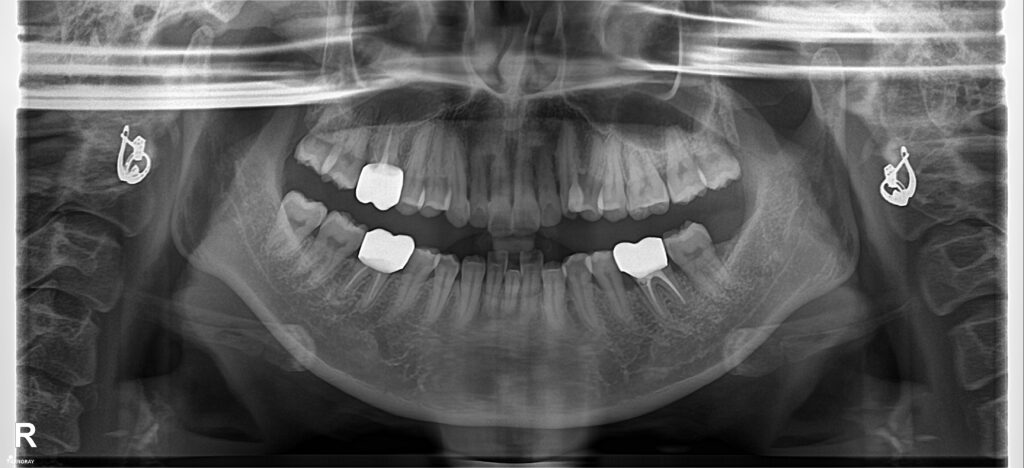

Một trường hợp điển hình của nhóm bệnh nhân hô hàm hô cả xương, lại có cả chen chúc răng. BN thiếu R31 bẩm sinh, sai khớp cắn hạng II chi 2 có chen chúc hàm trên như này thì rất dễ bị khớp cắn sâu nếu nhổ răng đều. Sau phân tích và tính toán thì BN được chỉ định nhổ 3 răng số 4 để kéo giảm hô.

Kết quả: sau 1.5 năm điều trị, BN được tháo niềng